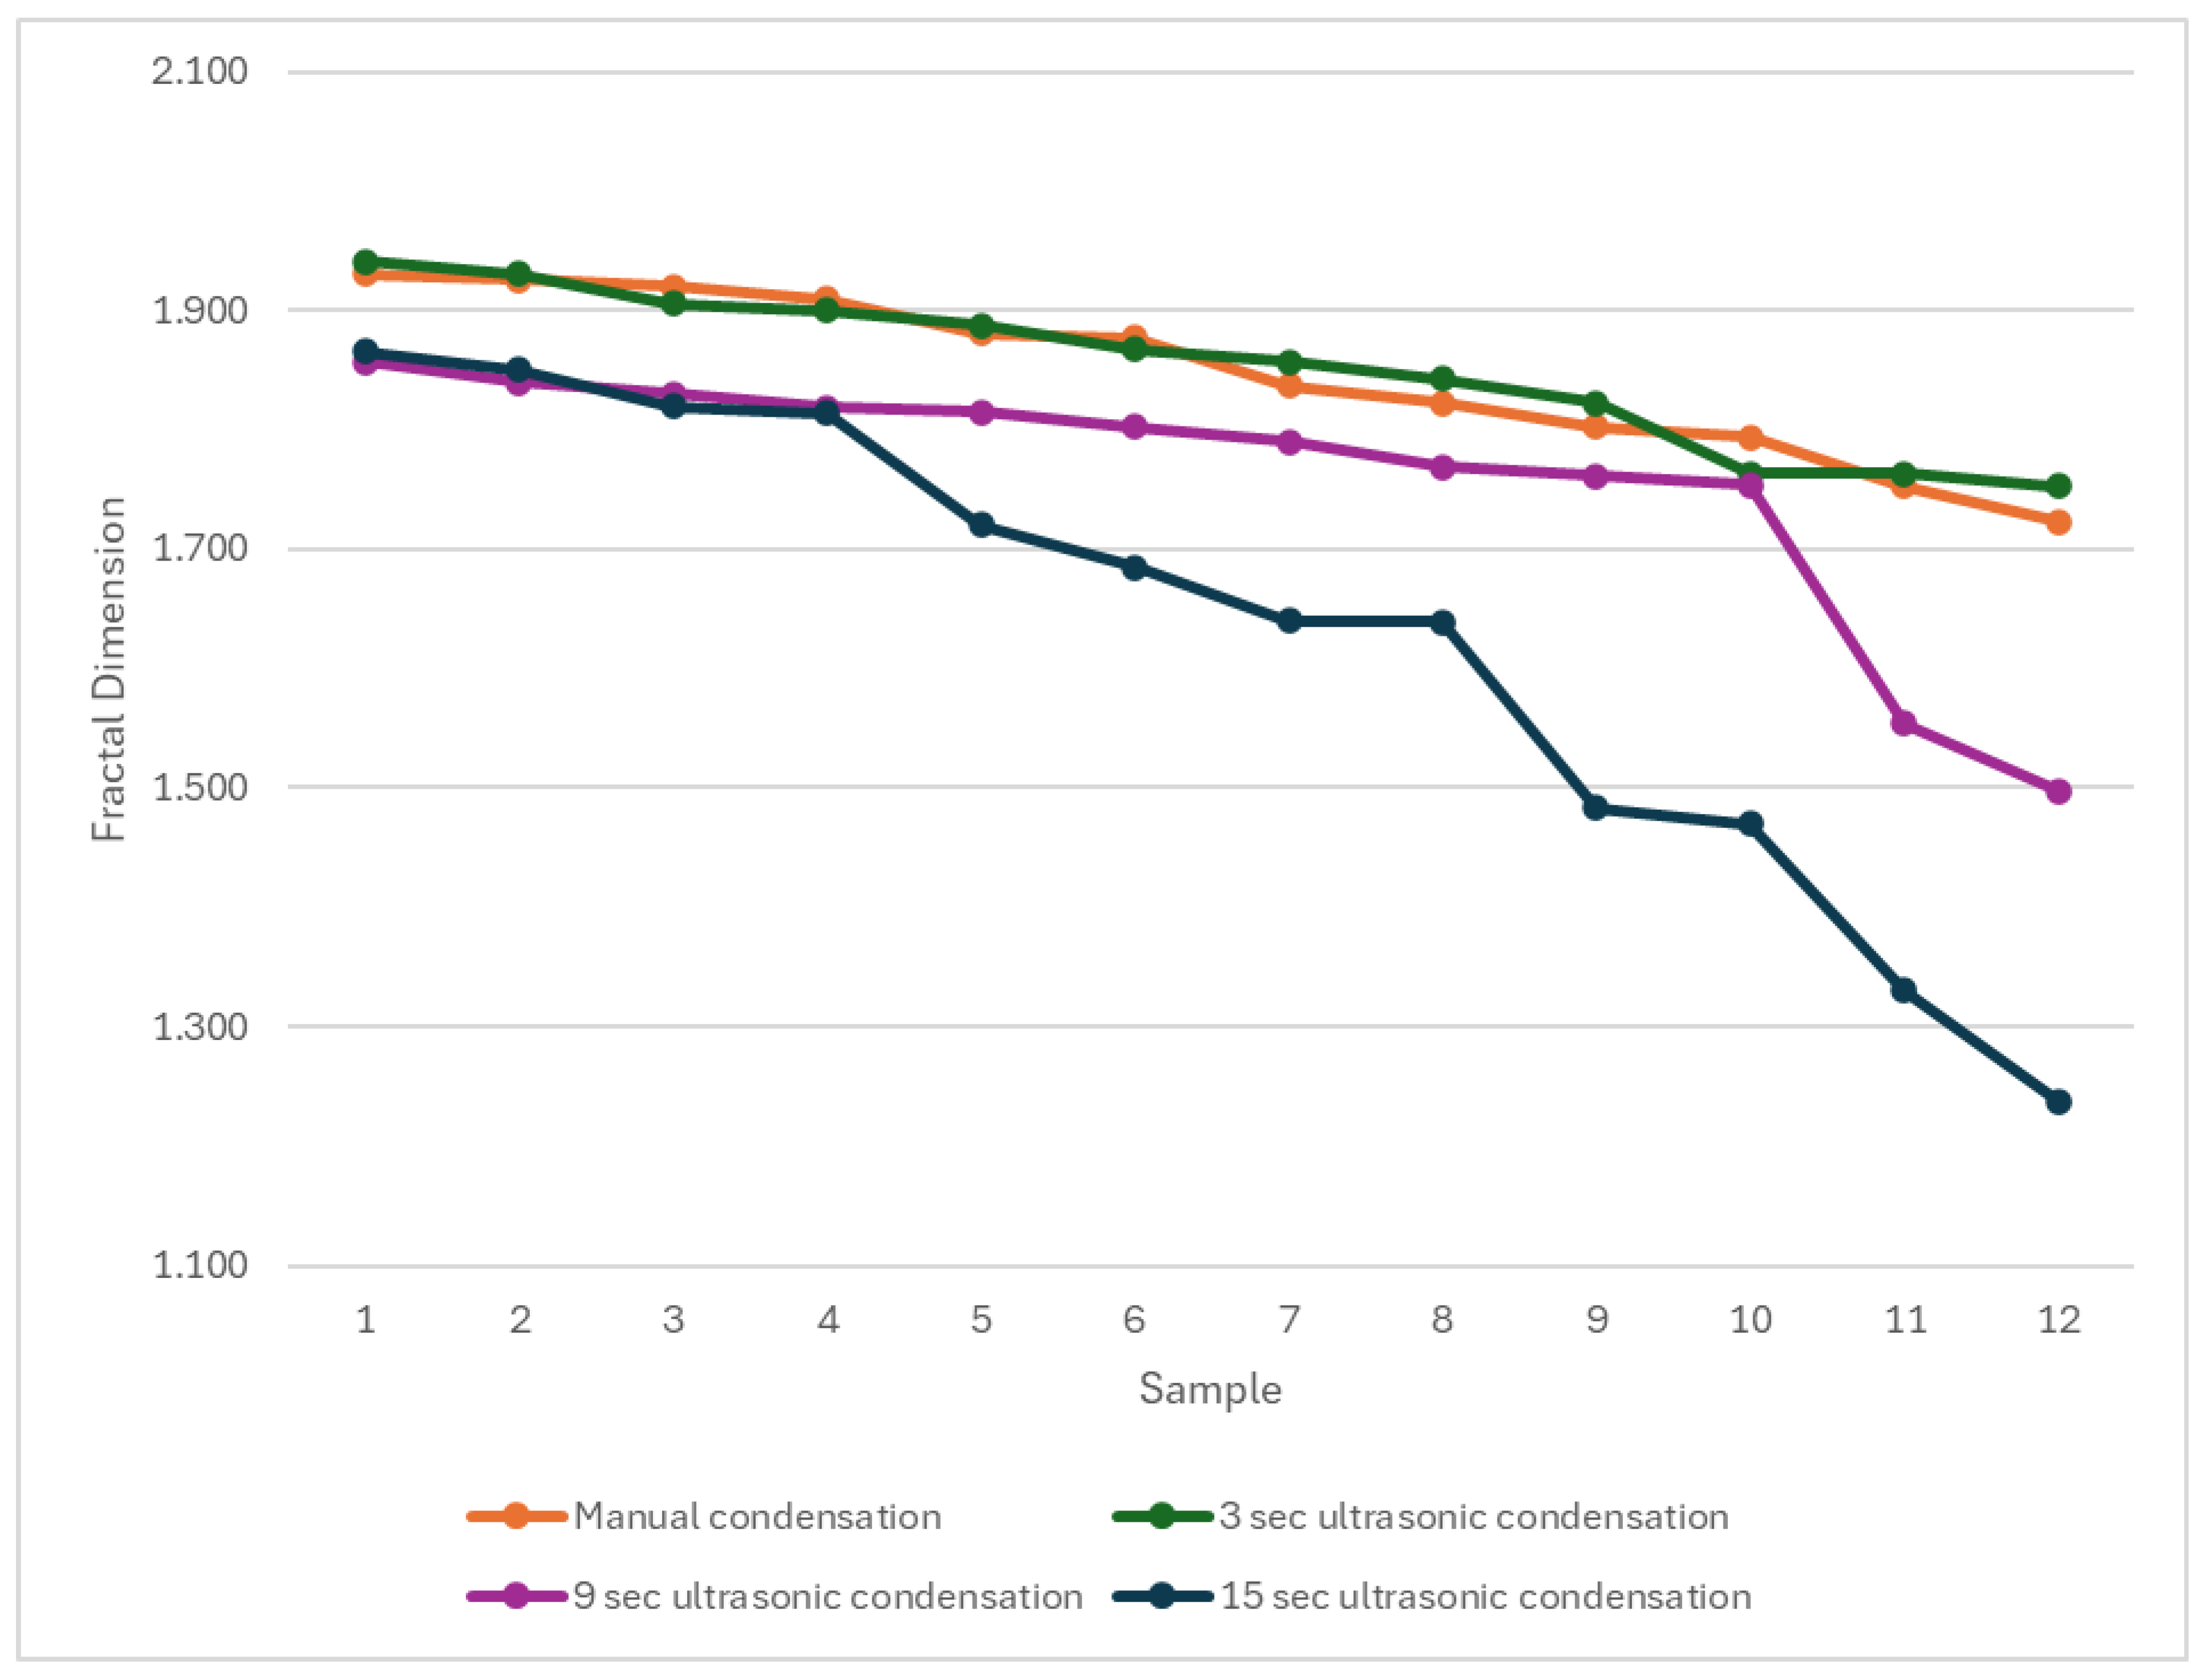

The fractal dimension analysis provides additional insight into the microstructural effects of ultrasonic condensation on Well-Root™ PT apical plugs by quantitatively characterizing the homogeneity and complexity of pore or void distributions within the material. The use of fractal dimension and multifractal spectral symmetry allows for a more nuanced assessment of pore structure than conventional metrics, as demonstrated in the ultrasonic characterization of heterogeneous media, where lower fractal dimension values are associated with less complex, more uniform void structures [

45]. The results in

Figure 5 suggests that prolonged ultrasonic condensation results in less complex voids compared to shorter activation. The significantly lower fractal dimension in Group 4 (15 s ultrasonic activation) suggests less complex void structures, potentially indicating larger, more uniform voids that could act as stress concentration points, compromising mechanical stability. This aligns with the increased external void volumes and reduced microhardness observed in Group 4, reinforcing the conclusion that prolonged ultrasonic activation is detrimental to apical plug quality. In contrast, the similar fractal dimensions in Groups 1 and 2 (manual and 3 s ultrasonic activation) indicate comparable void complexity, supporting the use of brief ultrasonic activation to achieve a dense, well-adapted apical barrier. These findings highlight the importance of optimizing condensation techniques to balance void morphology and material integrity, enhancing the long-term prognosis of endodontically treated immature teeth. The relationship between fractal parameters and ultrasonic attenuation further substantiates the utility of fractal analysis in evaluating the microstructural integrity of apical plugs subjected to ultrasonic condensation.